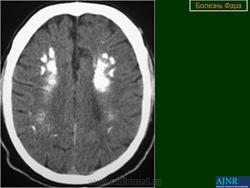

Основным методом прижизненной диагностики болезни Фара является КТ мозга, выявляющая симметричные участки резко повышенной плотности, располагающиеся в указанных выше структурах мозга. Иногда симметричные кальцификаты в виде точечных «вкраплений» могут быть видны на обычных рентгеновских снимках черепа, чаще в супраселлярной области на расстоянии 3-4 см от средней линии. Важно подчеркнуть, что при подозрении на идиопатическую кальцификацию базальных ганглиев важно проводить нейровизуализационное обследование ближайших родственников больного.